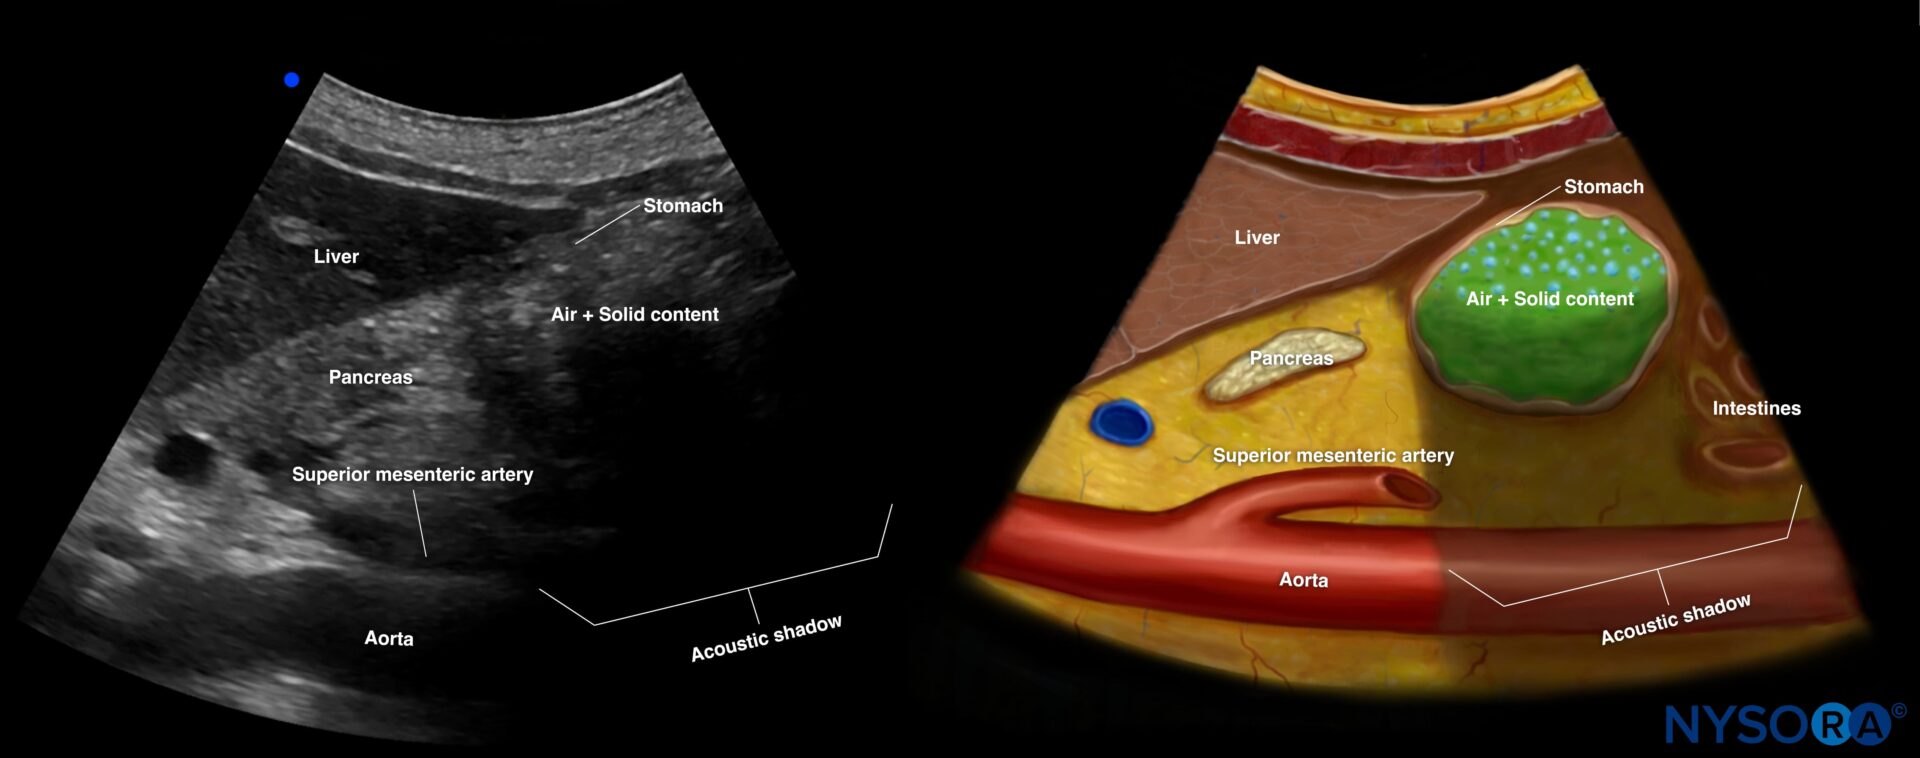

A comprehensive learning tool for anesthesiologists, emergency, and critical care physicians, offering structured modules across eight organ systems, including lung, cardiac, abdominal, renal, and vascular. It integrates step-by-step protocols with high-quality ultrasound images, videos, animations, and NYSORA’s Reverse Ultrasound Anatomy to simplify interpretation of normal and pathological findings.

Detailed anatomical illustrations and ultrasound images.

Reverse Ultrasound Anatomy illustrations for intuitive sonoanatomy recognition.

NYSORA’s proprietary Reverse Ultrasound Anatomy simplifies the understanding of sonoanatomy.

Gastric content assessment, vascular access, free intraperitoneal fluid, and more crucial bedside assessments.

Reverse Ultrasound Anatomy illustrations make sonoanatomy easier to understand and apply.